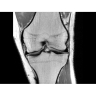

• РЧ-катушки, оптимизированные для исследования конкретных участков тела — элементы катушек высокой плотности располагаются вокруг исследуемых участков тела и при необходимости обеспечивают расширенный охват и оптимальное качество изображений при каждой процедуре.

• Широкое поле зрения — поле зрения шириной 50 см позволяет охватывать крупные анатомические области за меньшее число сканов.

Помимо перечисленных возможностей, системы с широкими туннелями открывают дополнительные пути для диагностики и терапии. Расширение возможностей позиционирования пациента и доступа к нему позволяет использовать новые интервенционные и хирургические процедуры.